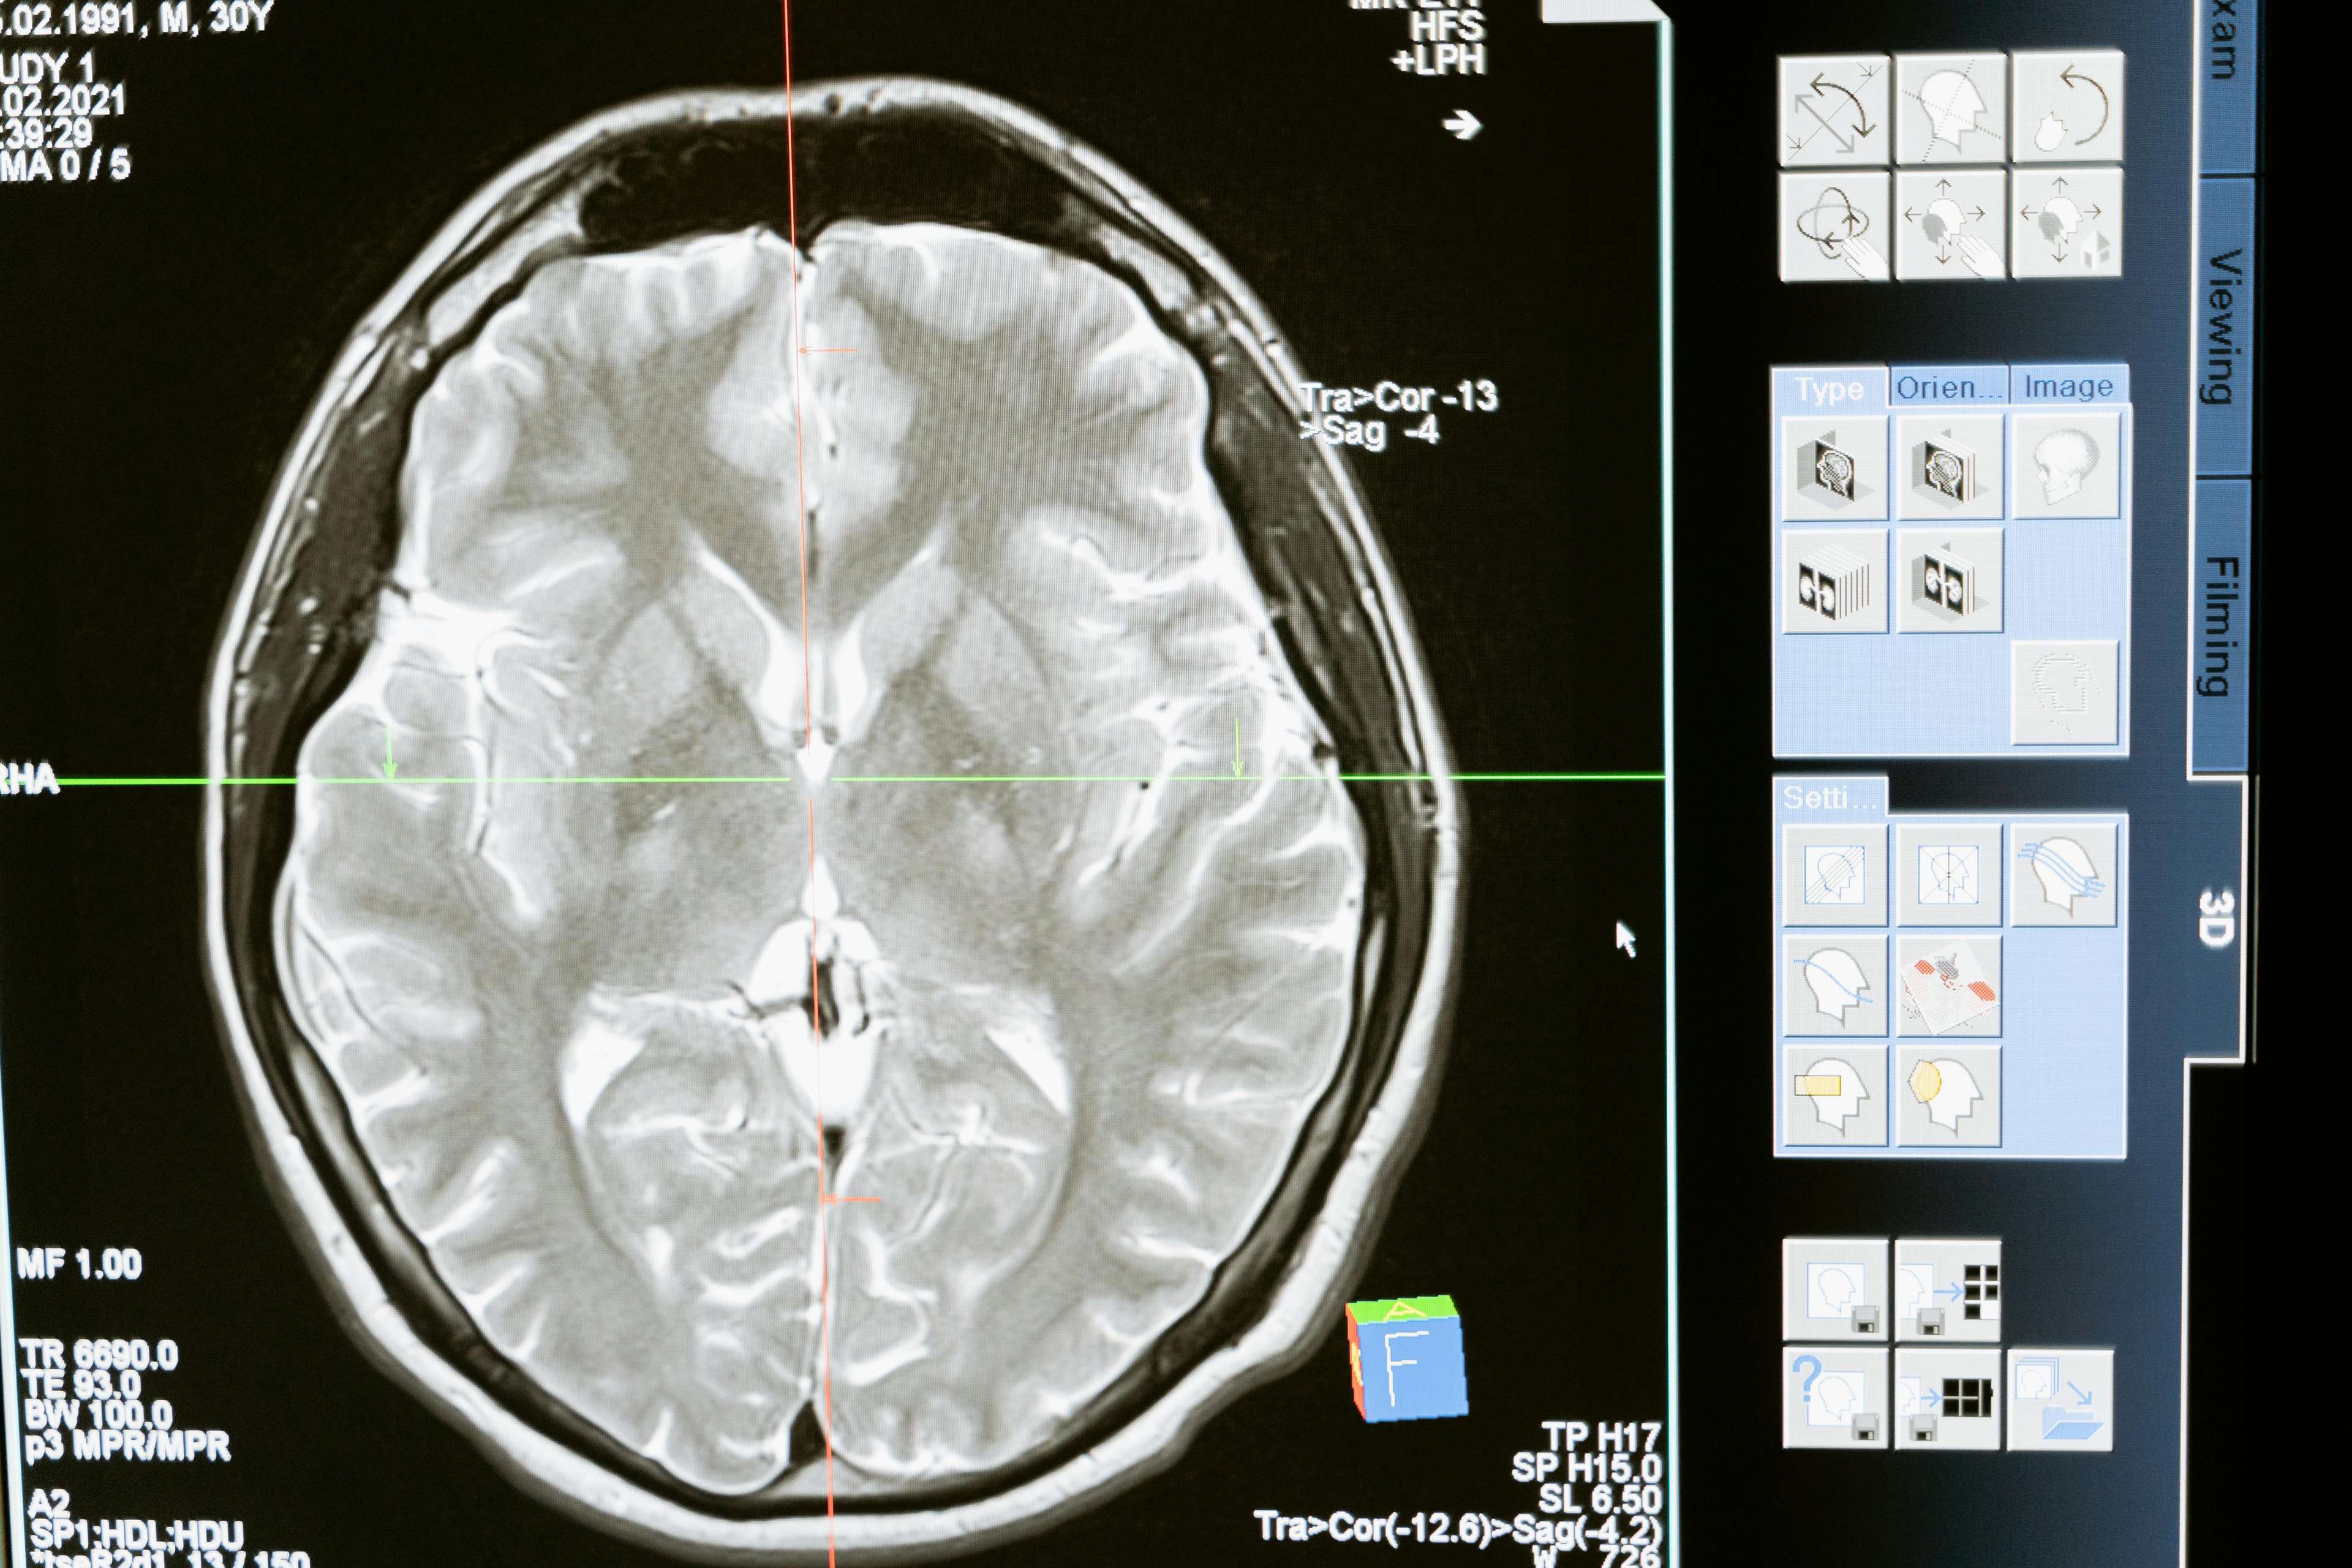

ጥልቅ የአእምሮ ማነቃቂያ የቀዶ ጥገና ሂደት ሲሆን ይህም የኤሌክትሪክ ግፊትን ወደ ተወሰኑ የአንጎል አካባቢዎች የሚልክ መሳሪያ መትከልን ያካትታል. ይህ የፈጠራ ህክምና የፓርኪንሰን በሽታ፣ ዲስቶንያ፣ ኦብሰሲቭ ኮምፐልሲቭ ዲስኦርደር እና የሚጥል በሽታን ጨምሮ የተለያዩ ሁኔታዎችን በማስተዳደር ረገድ ትልቅ እገዛ አድርጓል. የተወሰኑ የአንጎል አካባቢዎችን በማነጣጠር ጥልቅ የአንጎል ማነቃቂያ ያልተለመደ የአንጎል እንቅስቃሴን ለመቆጣጠር፣ ምልክቶችን ለማስታገስ እና የህይወት ጥራትን በእጅጉ ለማሻሻል ይረዳል. ውጤቶቹ ብዙም የሚያስደንቁ አይደሉም - በአንድ ወቅት በቤታቸው ታግረው የነበሩ ታካሚዎች አሁን በእግር መሄድ፣ መሮጥ እና ሙሉ ህይወት መኖር ችለዋል.